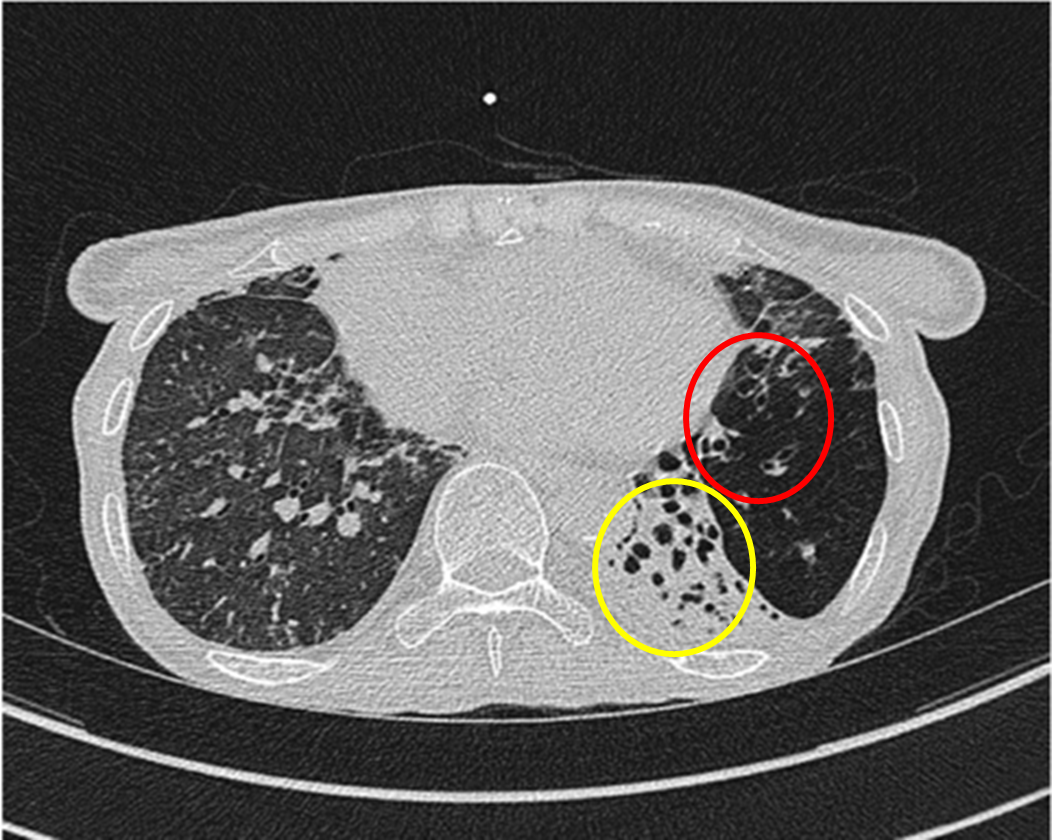

기관지 확장증, 주요 증상과 치료 방법 총정리

기관지 확장증은 기관지의 비정상적인 확장을 의미하며, 이를 경험하는 환자들은 주로 가래, 기침, 호흡 곤란 등의 증상을 겪게 됩니다. 이러한 증상들은 일상생활에 큰 영향을 미칠 수 있으며, 질병의 원인과 치료 방법에 대한 체계적인 이해가 더욱 필요합니다. 이번 포스트에서는 기관지 확장증의 주요 증상과 치료 방법을 총정리하겠습니다. 살면서 알레르기나 감기와 같은 사소한 건강 문제를 겪으면서도, 내 몸의 변화에 대한 소홀함이 후에 큰 문제가 될 수 있음을 잊지 말아야 합니다.